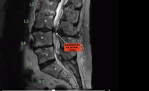

Have had the problem twice, latest was in early 2017, pain in left leg, gradually got worse to almost unbearable. To GP arranged an MRI same problem as on right leg 19 years earlier, SPINAL STENOSIS, narrowing of the Spinal Canal where the wiring harness passes through, (Spinal Cord), vertebrae pressing on a nerve.

Went to Spinal Specialist in Brisbane, (Bris Brain & Spine), who had done other side, 3 ½ hours surgery and like new again after a couple of months. Have more flexibility now than for years.

Removed offending piece of Vertebrae, fused 2 vertebrae, inserted 6 screws and plastic cage around it all. Previous occasion was on left leg 19 years earlier and he only needed to trim vertebrae on that occasion.

XRAY SPINE 1 2019-08-30 at 9.27.29 am.png

-- Edited by blissonwheels on Monday 22nd of June 2020 10:22:52 AM

Bliss that looks painful..

I hope I don't have that.

Hope you are much much better now.